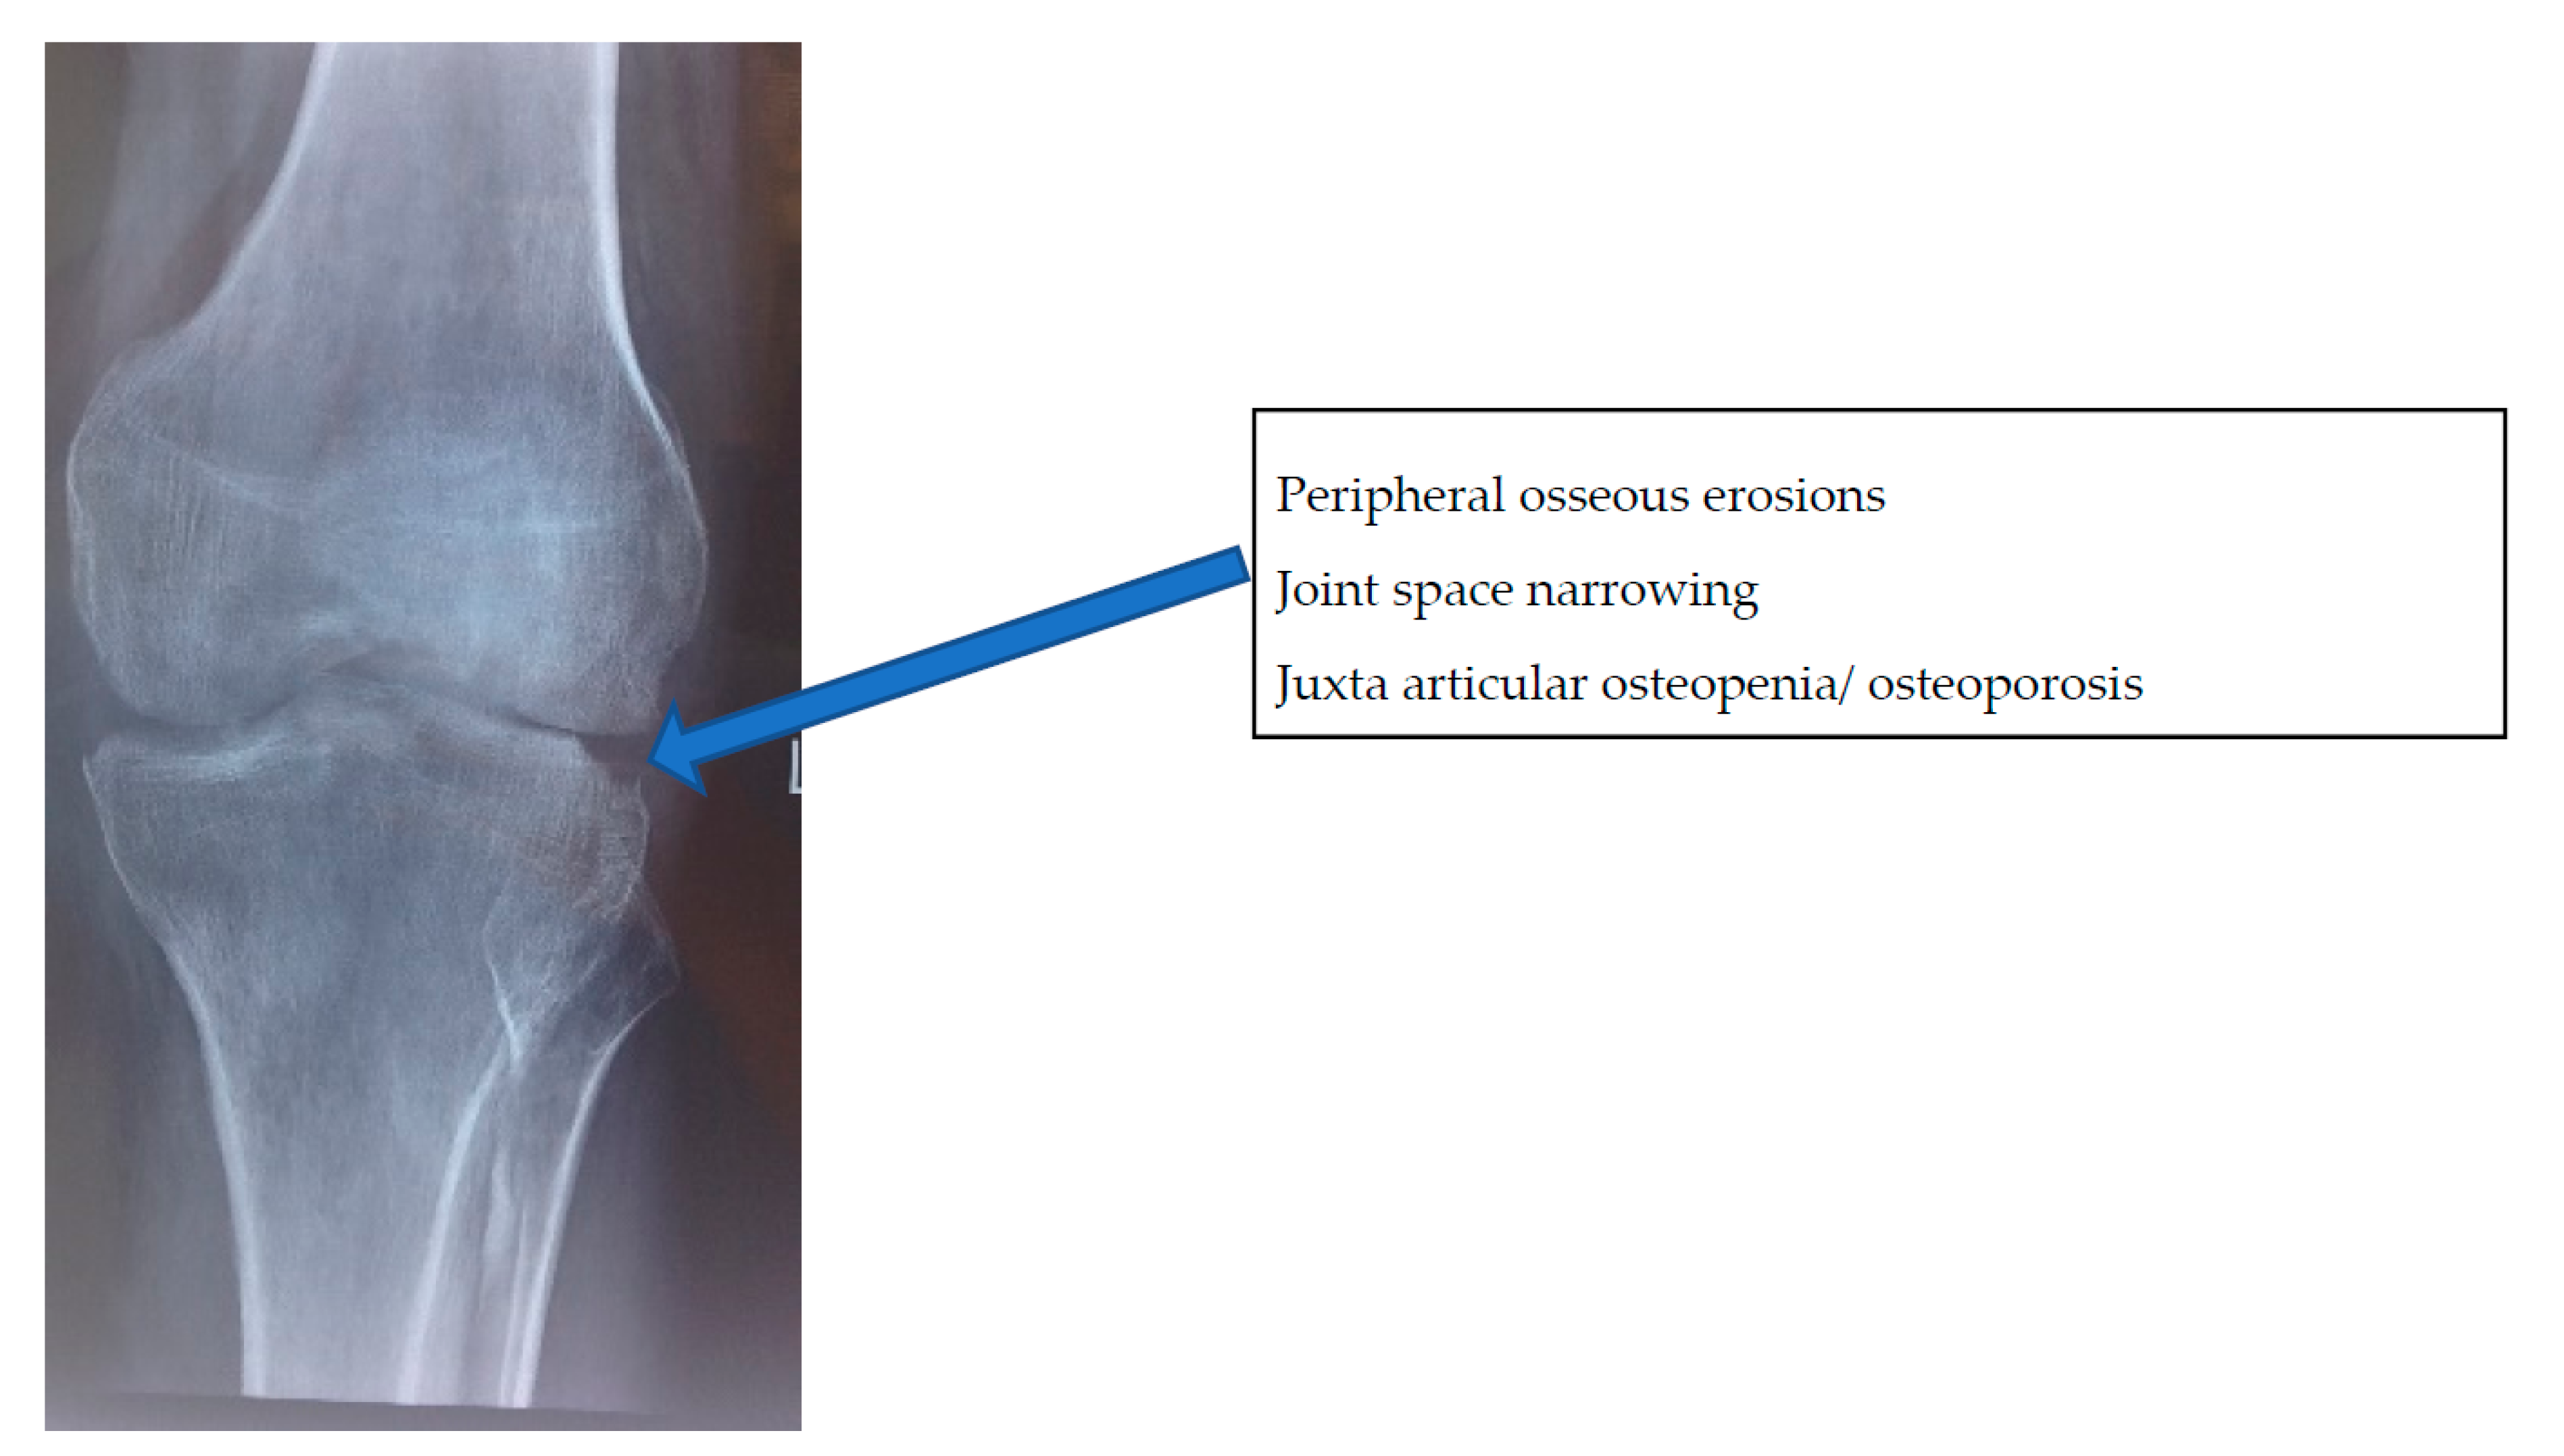

- Stage of early arthritis. Patient presents with joint pain, spasm of the surrounding muscle, and difficulty in doing some activities of daily living. Affected joint has 50–75% of the joint movement preserved. X-ray shows classical Phemister’s triad of juxta-articular osteopenia, mild joint space reduction, and peripheral osseous erosions. This stage has good prognosis with mild stiffness.

2.2. Imaging Features